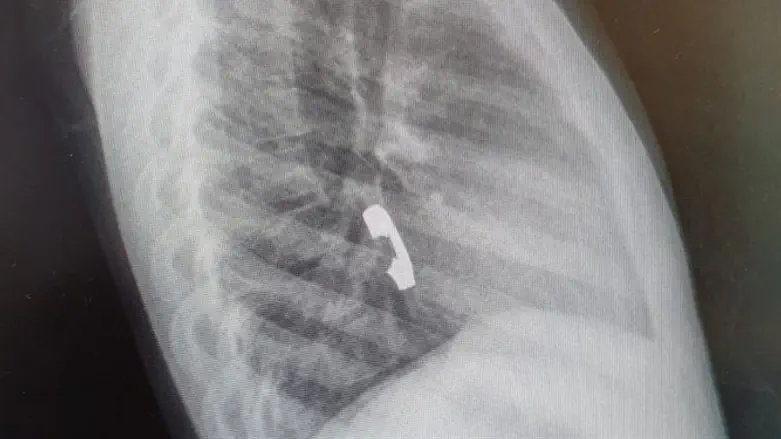

לאחר שחשה כאבים באיזור החזה היא הובהלה לבית החולים, שם בוצעו לה צילומים שהראו כי הטבעת נתקעה בושט. בעקבות האבחנה הוחלט לבצע פעולת גסטרוסקופיה בהרדמה מלאה להוצאת הטבעת.

בשל היותה של הטבעת חתוכה, נדרשה תשומת לב גדולה יותר ורמת דיוק גבוהה, על מנת שלא לפצוע את הנתיב בו הוצאה הטבעת החוצה.